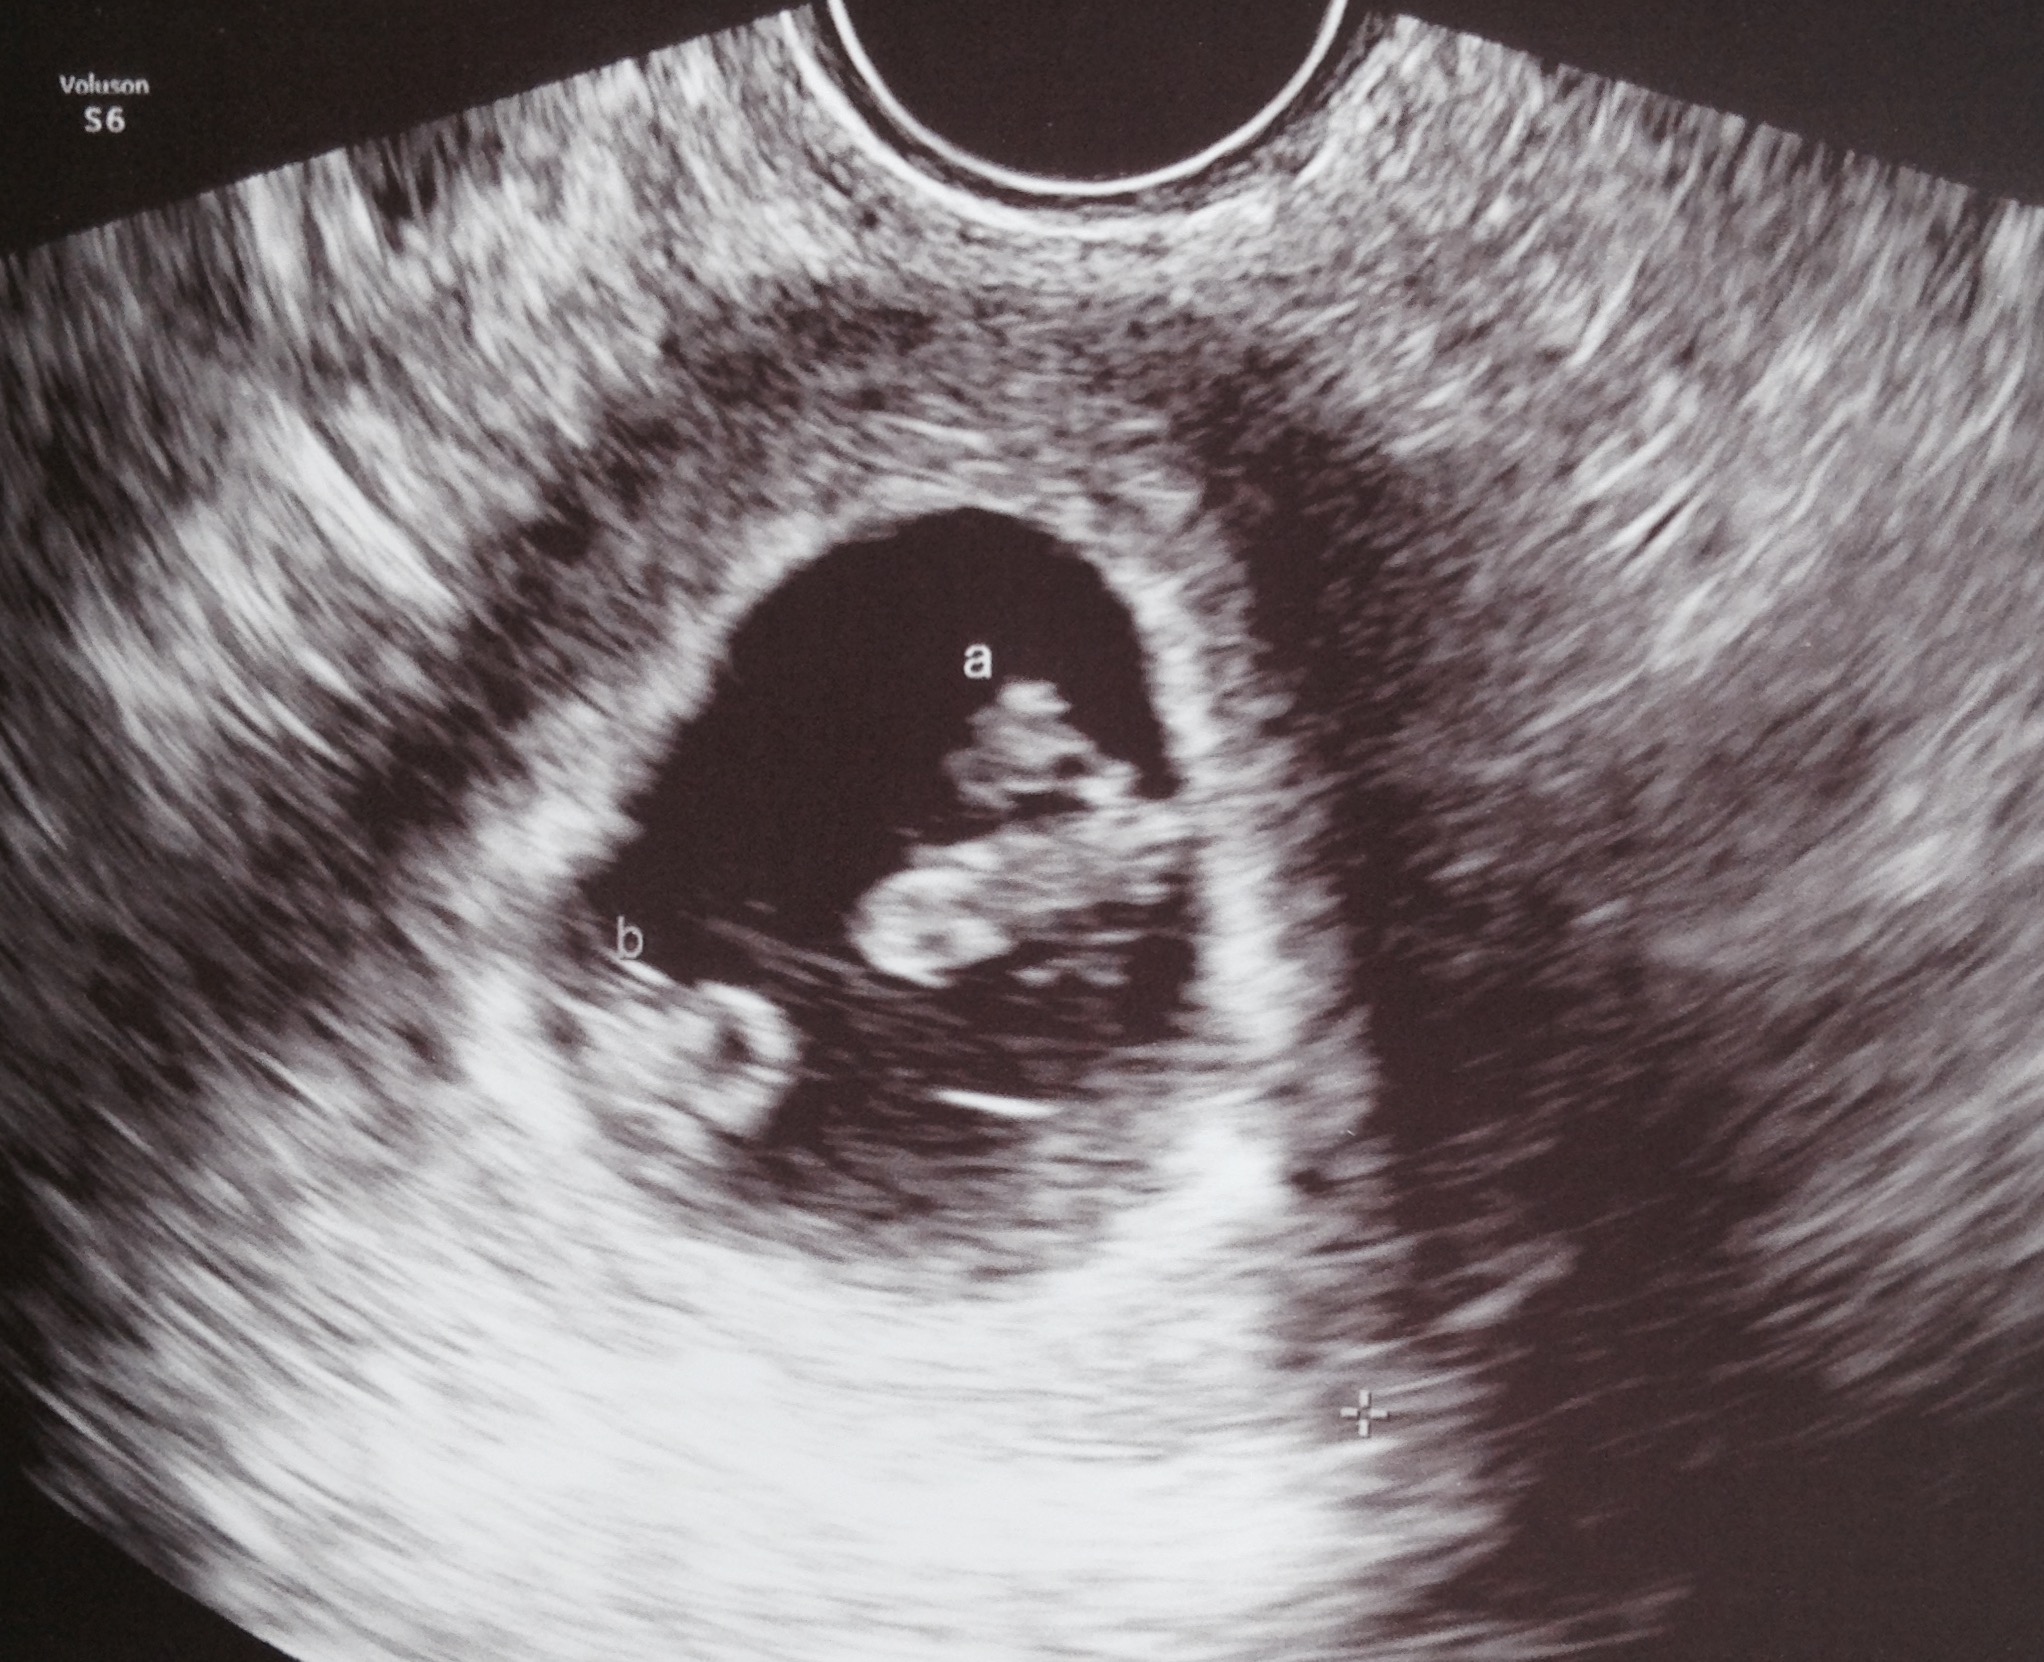

We had our first ultrasound today at 7w5d after IVF with transfer of ONE embryo. Imagine our surprise when we saw TWO babies! Identical twins - we are still in shock and yet so excited! We saw both heartbeats, which was indescribably amazing. We will have another US on 11/20 (8w6d) before graduating from our RE to our OB.